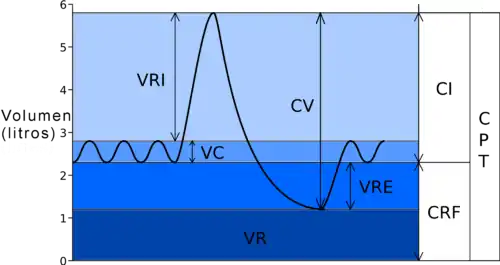

Volúmenes pulmonares

En condiciones normales, una persona respira 15 veces por minuto y en cada inspiración entra en sus pulmones 500 cc de aire. En la espiración sale del pulmón la misma cantidad que entró. Por lo tanto en un minuto la ventilación pulmonar es 15 x 500 = 7.5 litros, que es lo que se llama volumen minuto. Sin embargo, la profundidad de las respiraciones y su frecuencia puede aumentar considerablemente en condiciones de esfuerzo físico, por lo que el volumen minuto puede llegar hasta los 200 litros por minuto, multiplicando el valor en reposo más de 20 veces.[11]

- Volumen corriente (VC): Es la cantidad de aire que se utiliza en cada respiración no forzada. Es aproximadamente de 500 ml. Esto significa que en condiciones normales durante una inspiración entran 500 cc de aire en los pulmones y durante la espiración sale la misma cantidad.

- Volumen de reserva espiratorio. Corresponde al volumen extra de aire que se puede expulsar hacia el exterior cuando se realiza una espiración forzada. Su valor medio es 1000 cc.

- Volumen de reserva inspiratorio. Corresponde al volumen extra de aire que se puede inhalar cuando se realiza una inspiración forzada. Su valor medio es 2500 cc.

- Volumen residual. Corresponde a la cantidad de aire que queda en el interior del pulmón después de una espiración máxima. Su valor medio es 1200 ml.

La capacidad pulmonar total viene dada por la suma de los 4 volúmenes anteriormente citados.